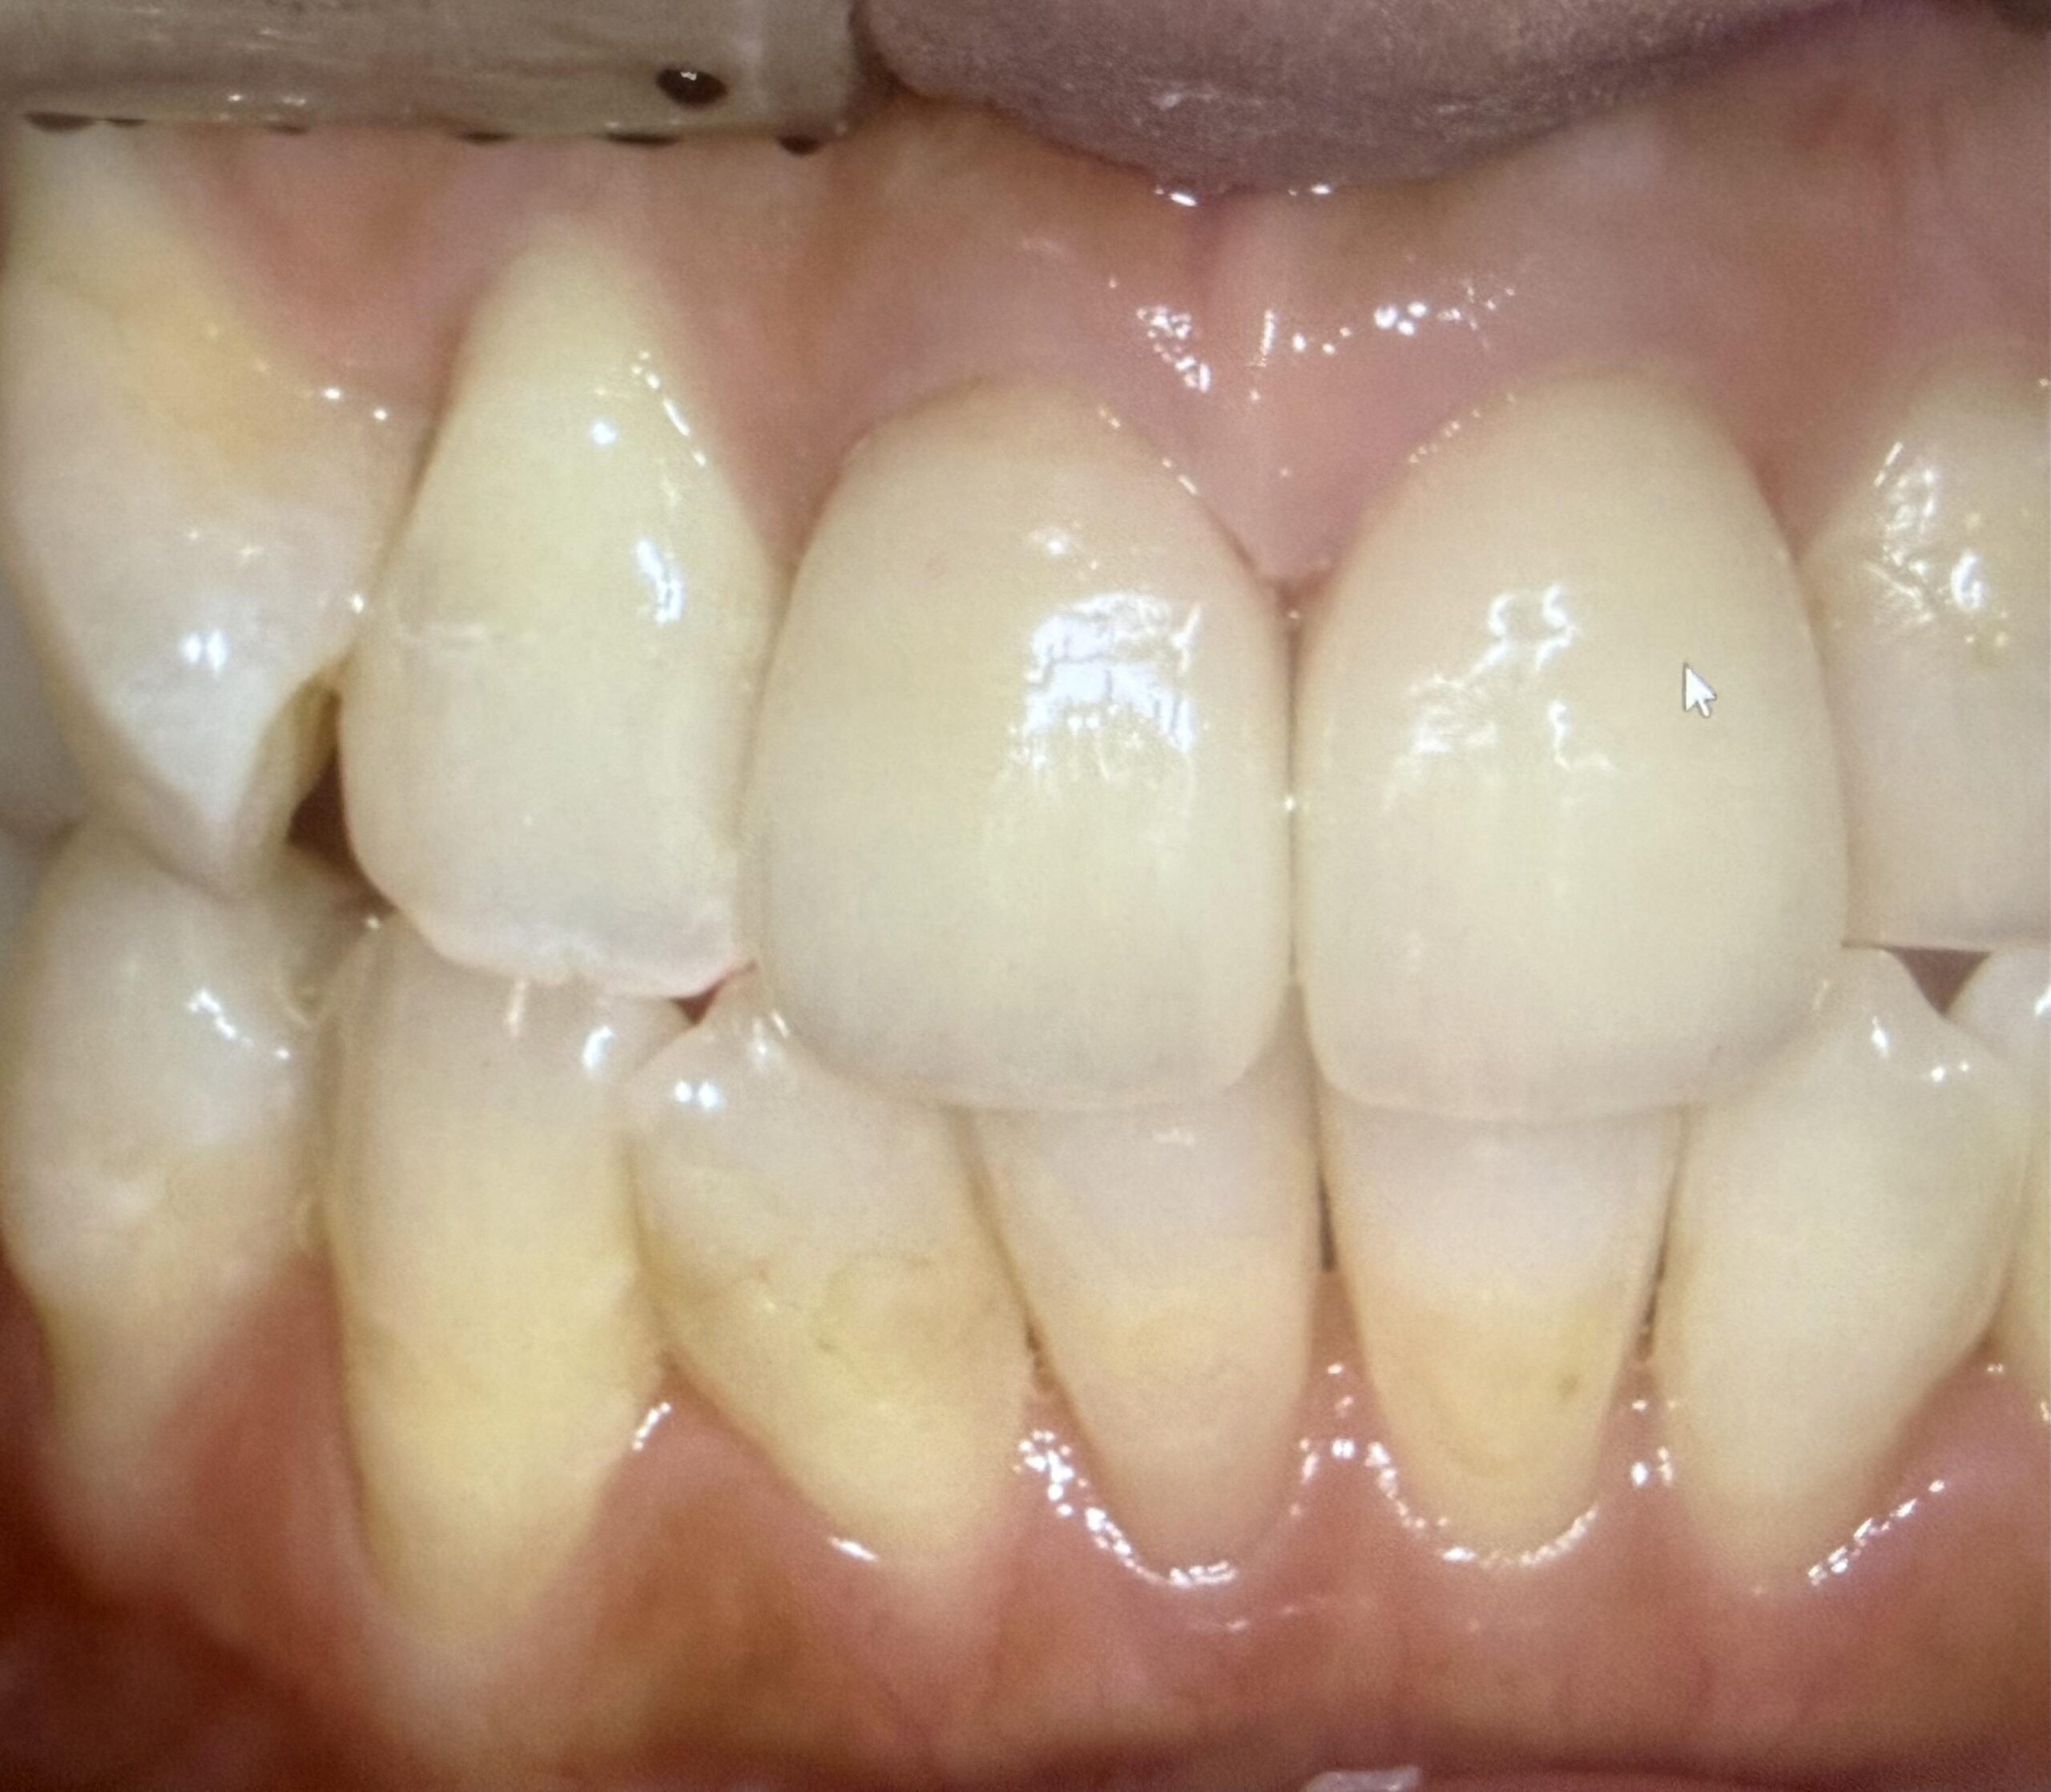

下の歯が上に上がってきている。上の歯が下に降りてきた。

それ、実はよくある現象です。結論からいうと「歯が伸びた」のではなく、噛み合う相手がいなくなって歯が動いてきた状態です。

この現象は歯科では挺出(ていしゅつ)と呼ばれます。

一番後ろの7番目の歯が抜きっぱなしになっているケースは特に多く感じます。

虫歯や、脱離で上の部分がなくなり、根っこだけが残っている場合も同様のことが言えます。